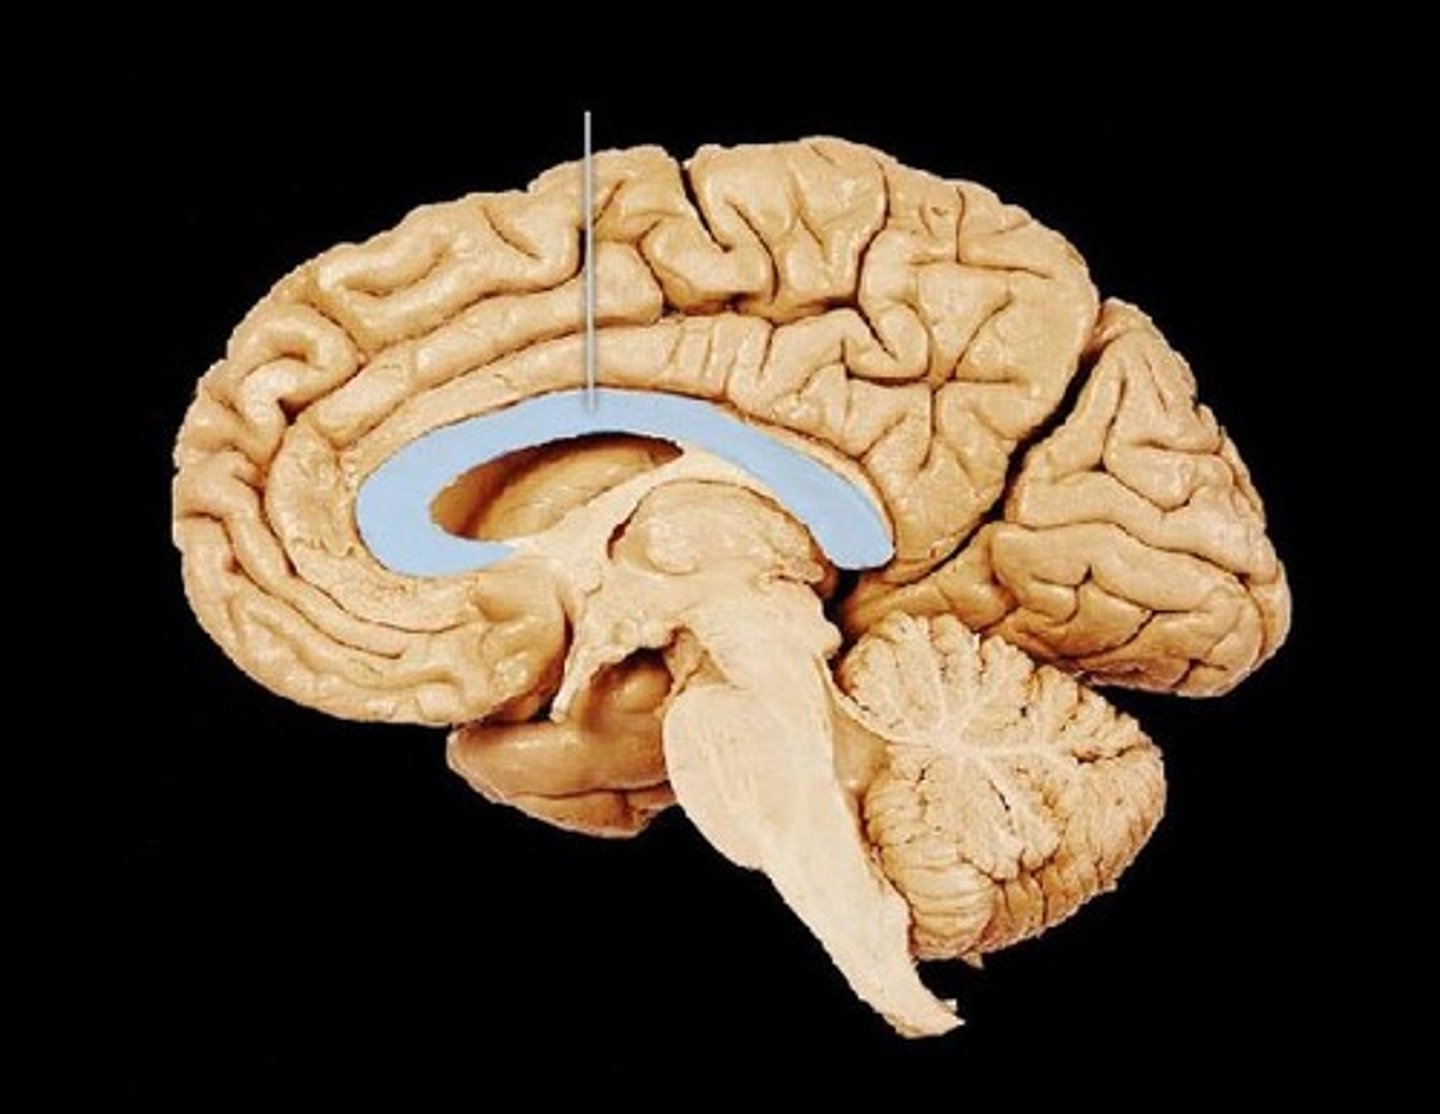

Corpus Callosum

Part of the limbic system. Band of nerve fibers which connect the 2 hemispheres of the brain